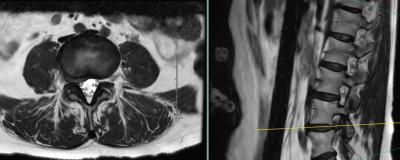

Preoperative MRI showing far lateral and foraminal right L4-5 disc herniation

Her imaging demonstrated a sizable paracentral and far lateral disc herniation on the right side at L4-5. She had obtained an initial opinion at a neighboring tertiary care academic medical center who recommended a fusion as they felt that a total facetectomy was needed to fully decompress the existing and traversing nerve root.